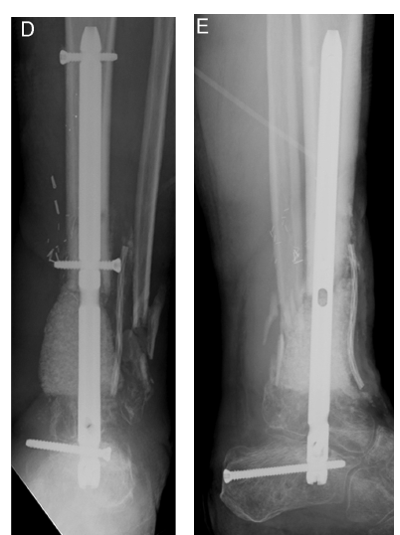

Stage II取出Spacer   混合材料植骨    仔细缝合软组织覆盖良好

髓内钉内固定踝关节融合

技术改进Stage I   直接使用内固定

长节段骨缺损使用Cage作为局部植骨支架

17cm骨缺损